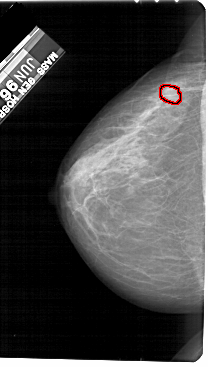

FILE: A_1524_1.LEFT_CC.OVERLAY

TOTAL_ABNORMALITIES 1

ABNORMALITY 1

LESION_TYPE MASS SHAPE OVAL MARGINS ILL_DEFINED

ASSESSMENT 4

SUBTLETY 2

PATHOLOGY MALIGNANT

TOTAL_OUTLINES 1

BOUNDARY